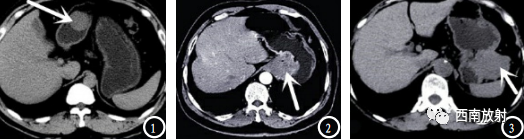

▲病例:胃肠道不同部位的间质瘤形态表现。([2]廖 月.胃肠道间质瘤患者 超声和MSCT征象特 点分析[J].中国CT和MRI杂志.2019.17(1):101-103.)

▲小肠间质瘤,肿块巨大,超过10cm,实质内见多发钙化灶;

▲小肠间质瘤,肿块巨大,超过10cm,实质内见多发钙化灶;动脉期肿块不均匀强化,见斑片状坏死区及环状或花边状改变[4]。

▲小肠间质瘤,肿块巨大,超过10cm,实质内见多发钙化灶;动脉期肿块不均匀强化,见斑片状坏死区及环状或花边状改变。静脉期强化更加明显。

▲小肠间质瘤,高度危险性。肿块术中所见。肉眼所见,腹腔肿物:灰白肿物1个与一段小肠相粘连,肿物大小15*13*10CM,表面光滑,切面灰白质脆,小肠长14CM,直径3CM,与肿物相粘连长6CM,肠腔未见肿物及溃疡。